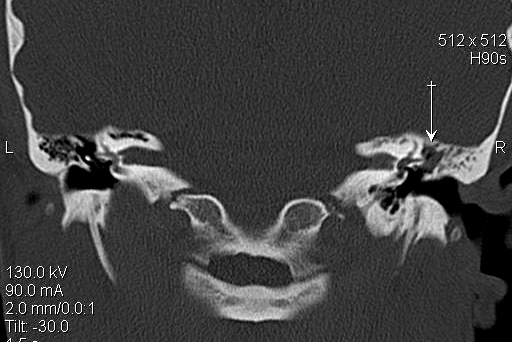

TC exostosis occipital congénica.

TC exostosis occipital congénita.